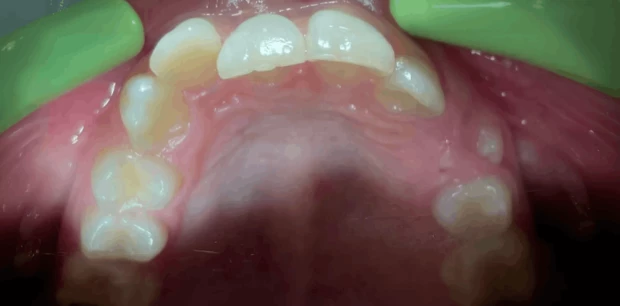

Ортодонтия

Ортодонтическое лечение элайнерами

Пациент И., 10 лет. Родители обратились с жалобами на неровные зубы сына. Проведено ортодонтическое лечение элайнерами. Лечение проводилось 1,5 года.